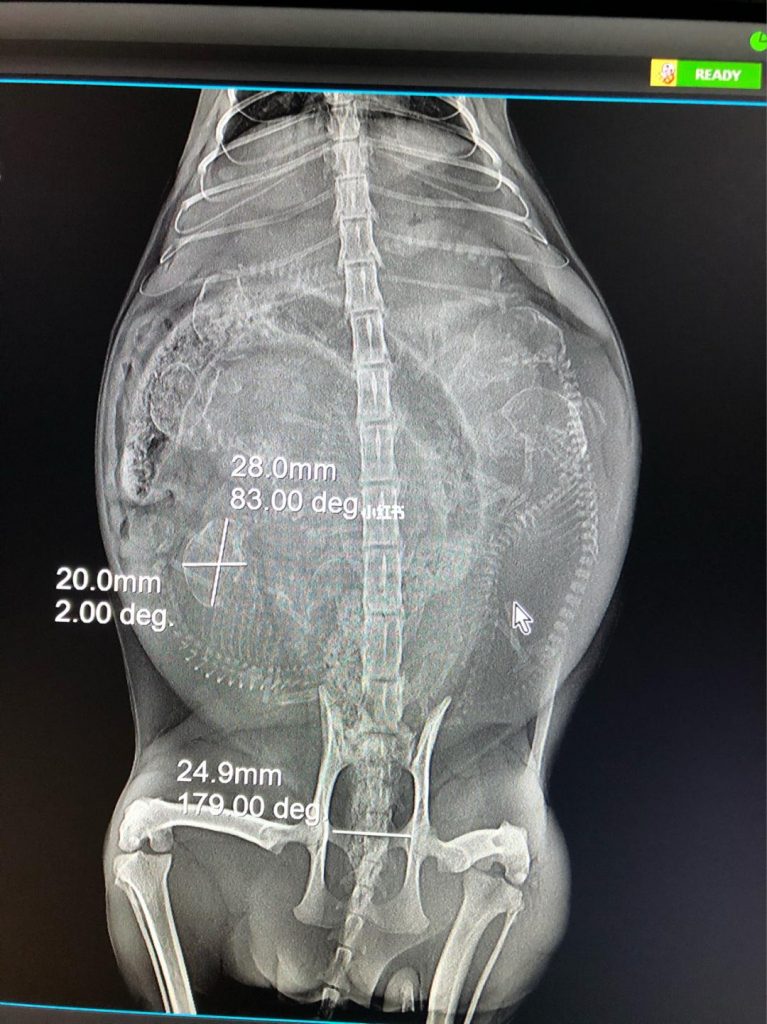

先让有经验的医生触诊,初步断定母猫是否需要刚怀孕,首先排除假孕。初判有孕后,给母猫共有拍两张正面和侧面的X光(拍片时间一般操纵在五十天左右,时间越晚小猫正常发育得越明显,但太晚了不便移动母猫外出)。拍片是可以探听到怀孕的小猫只数,以便接生的时候观察是否需要生产完毕后。

再询问医生母猫的产道与小猫头骨的宽窄,确认导致难产的可能性,先对能不能剖腹产/有无要破腹产心里有数。3.准备生产需要的物品